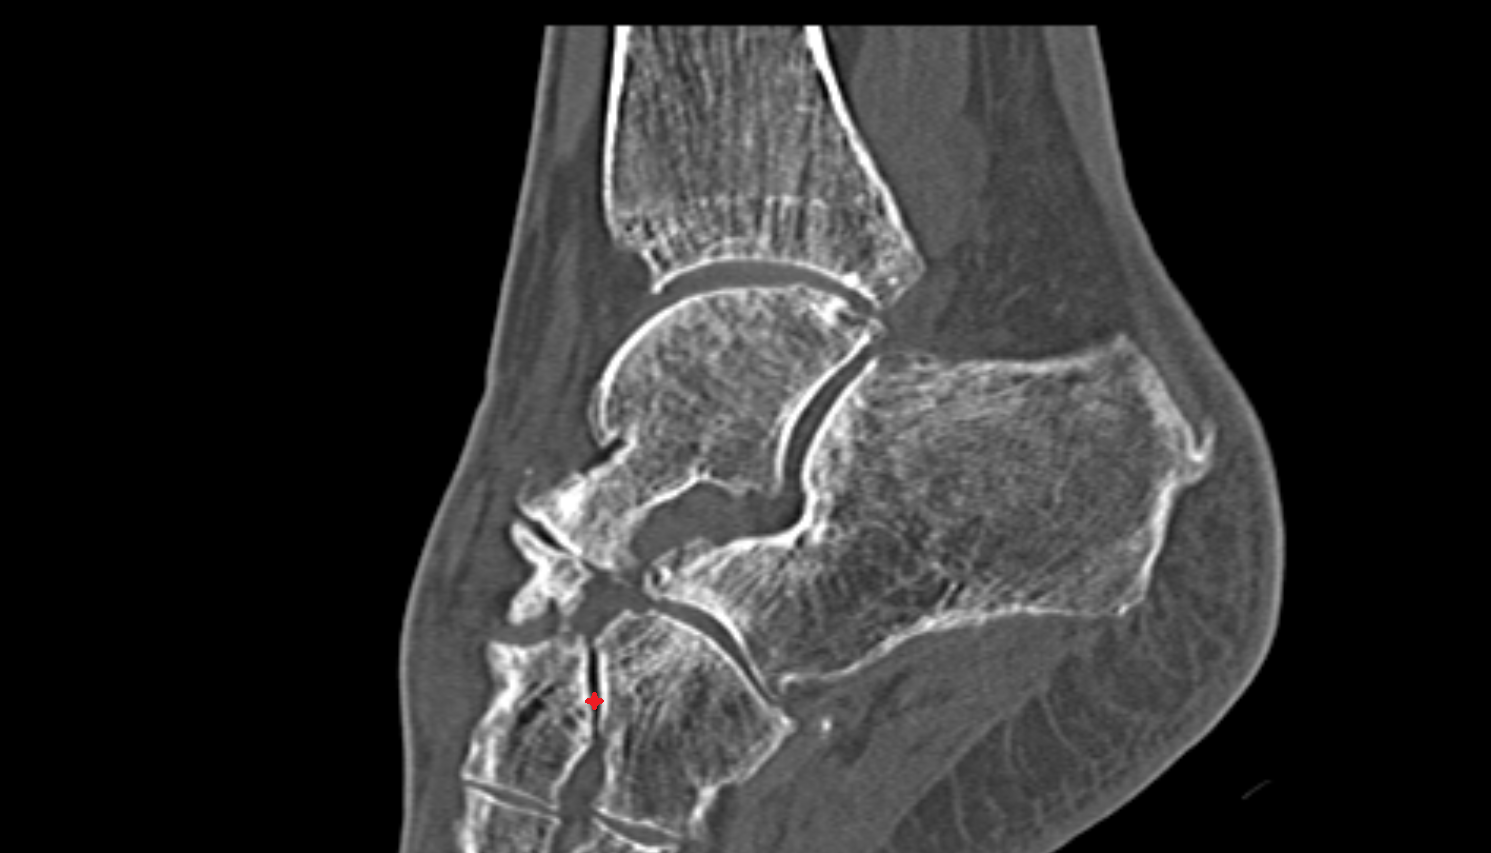

- Talus

- Head of talus

- Body of talus

- Neck of talus

- Calcaneus

- Anterior process of calcaneus

- Sustentaculum tali

- Ankle joint

- Talocalcaneal joint

- Talocalcaneonavicular joint